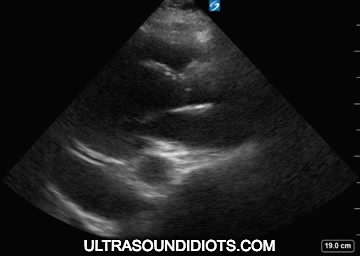

Parasternal Long Axis views of pericardial effusion

parasternal short axis views of pericardial effusion

Apical Views of pericardial effusion

subcostal views of pericardial effusion